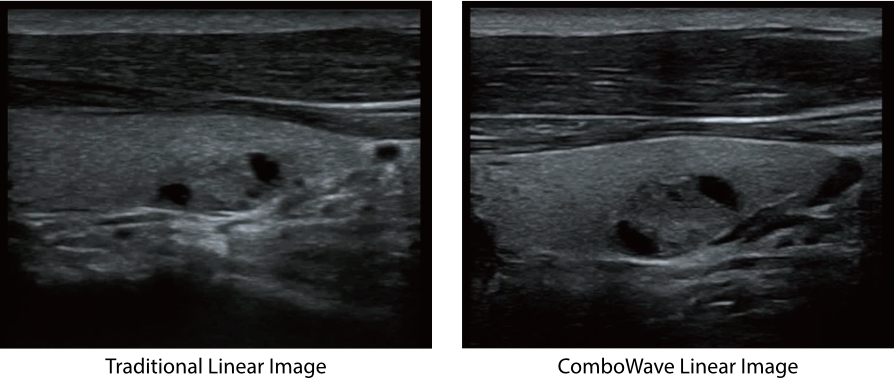

ComboWave ?????

?? ?????? ???? ComboWave ?????? ??? ??? ?? ?? ??? ???? ?? ????? ??? ????? ?? ????? ??????. ????? ??? 3T ??? ?? ??? ComboWave ??? ?????? ???? ???, ??, ?? ??? ??? ?? ???? ????? ??? ??? ??? ? ????.